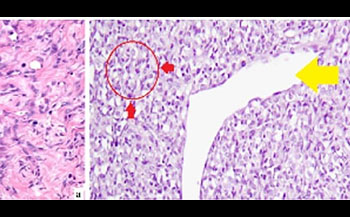

МРТ исследования головного мозга и DSC-перфузия. В области левого кавернозного синуса экстрааксиальное образование, с широким прилежанием к ТМО, окруженное перифокальным отеком и масс-эффектом на медиальные отделы височной доли левого полушария головного мозга. При анализе Т2 и Т2flair изображений, визуализируется особенный симптом «Инь-Ян», характеризующийся наличием двух компонентов у опухоли, один из которых гипоинтенсивный (гипоклеточная часть, представленная коллагеновой стромой), а другой гиперинтенсивный (гиперклеточная часть) по отношению к мозговой паренхиме. Кроме того данное образование демонстрирует гомогенное, относительно однородное накопление парамагнетика на постконтрастных изображениях, а так же наличие диспластически расширенных сосудов опухоли на SWI последовательностях, что отчетливо подтверждается высоким кровоснабжением данной опухоли на перфузионных картах с высокими значениями rCBV. Бесконтрастная Кт – демонстрирует неоднородную опухоль с наличием в структуре кальцинатов.⠀В настоящее время нет никаких патогномоничных признаков в диагностике данной опухоли, но симптом «Инь-ян» и выраженное гетерогенное контрастирование могут внести определенный вклад в диагностике данного образования.⠀Солитарная фиброзная опухоль (послеоперационный микропрепарат), окраска гематоксилином и эозином, увеличение х10. а – гипоклеточная зона образования, представленная прослойками коллагена (черные стрелки). б – гиперклеточная зона (красные стрелки), а так же наличие тонкостенных диспластично расширенных ветвящихся сосудов по типу «рогов оленя» ("staghorn" sign)